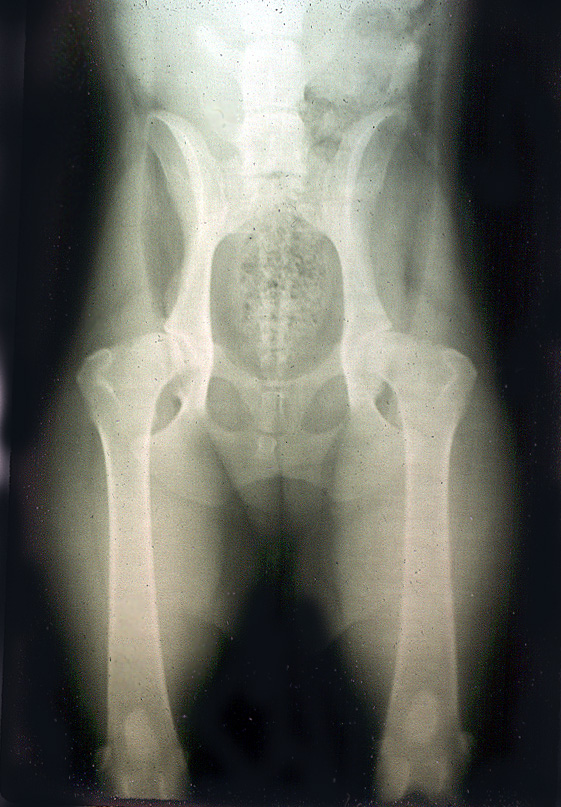

Product code: Mini aussie 2025 hip dysplasia

Hip Dysplasia Australian Shepherd Health Genetics Institute 2025, Hip Dysplasia Australian Shepherd Health Genetics Institute 2025, Hip Check Australian Shepherd Health Genetics Institute 2025, Facts About Dog Hip Dysplasia 2025, Dealing With Hip Dysplasia in Australian Shepherds AussieBase 2025, Hip Dysplasia and Australian Shepherd Hip Problems Ortho Dog 2025, Best Dog Food for Australian Shepherds 2024 2025, Hip Dysplasia in a Dog Symptoms Causes Treatments STOKESHIRE 2025, Australian Shepherd with Hip Dysplasia Nzymes 2025, Hip Dysplasia and Australian Shepherd Hip Problems Ortho Dog 2025, Australian Shepherd Dog Breed Health and Care PetMD 2025, Australian Shepherd with Hip Dysplasia Nzymes 2025, Hip Check Australian Shepherd Health Genetics Institute 2025, The Ultimate Guide to Caring for an Australian Shepherd 2025, Hip Dysplasia Dogs Life With Aspen 2025, Miniature Australian Shepherds Steemit 2025, Australian Shepherds Beautiful Colorful Arthritis Issues 2025, Australian Shepherd Dog Breed Information Characteristics 2025, Australian Shepherd dog breed information cost ManyPets 2025, Mini Australian Shepherd 24 Amazing Facts About Mini Aussie by 2025, Mini Aussie Breed Description Florida Fur Babies 2025, Australian Shepherds Wag 2025, Miniature American Shepherd Dog Breed Information and Characteristics 2025, Mini Aussies Frequently Asked Questions 2025, Dealing With Hip Dysplasia in Australian Shepherds AussieBase 2025, Miniature American Shepherd Wikipedia 2025, Mini Australian Shepherd Breed Information Premier Pups 2025, Spay Neuter Information In Relation To Hip Dysplasia TK Rocks 2025, Miniature Australian Shepherd Information and Pictures PetGuide 2025, Common Australian Shepherd Health Problems Canna Pet 2025, Is Your Mini Australian Shepherd Aggressive or Anxious Calming Dog 2025, Australian Shepherds 7 Things Only Aussie Owners Know 2025, Australian Shepherd vs Mini Australian Shepherd Comparison 2025, Ensuring Your Australian Shepherd Will Live a Longer Fuller Life 2025, 6 Most Common Australian Shepherd Health Issues 2025.

Mini aussie 2025 hip dysplasia